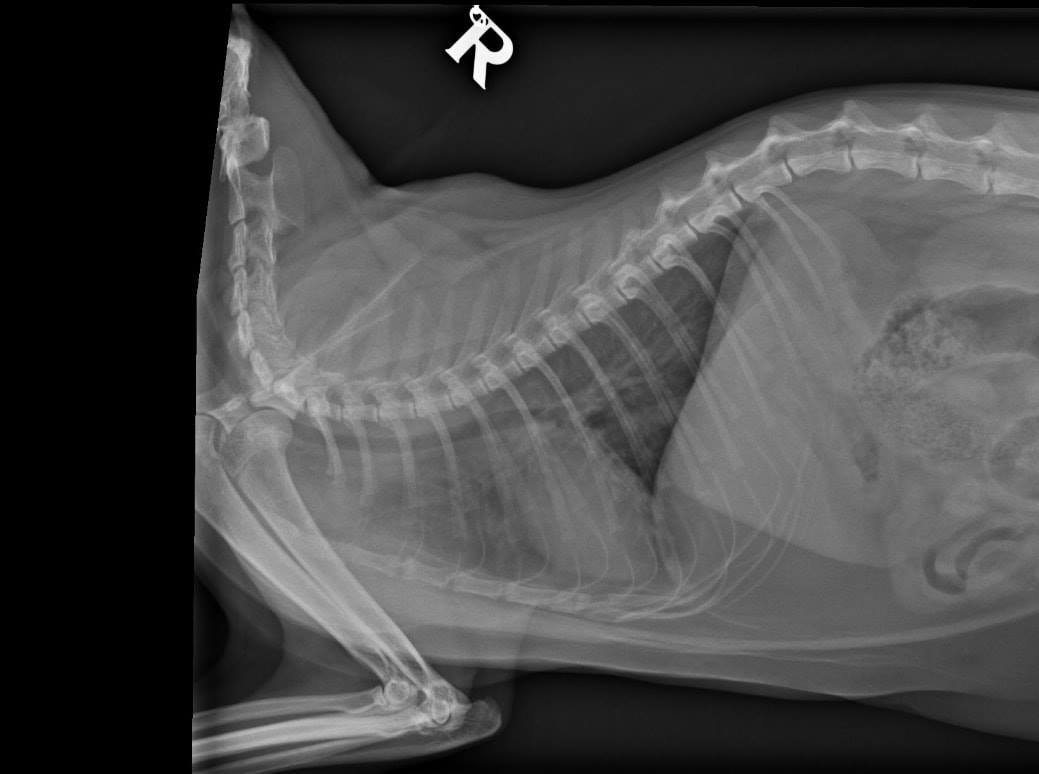

Po sérii vyšetření a RTG byla Donikovi nasazena chemoterapie! 😯

Drobné útvary nádoroveho bujení po celých plicích potvrdila i biopsie.